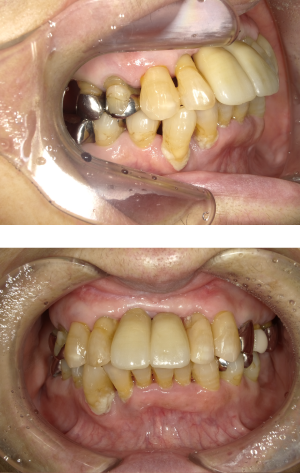

50代 インプラント治療(右上3左上3のみGBR)

| 年代・性別 | 50代・男性 |

| 主訴 | 入れ歯が合わず毎日ヨーグルトしか食べることができないので、しっかり咬めるインプラントにしたい。 |

| 部位 | 右下⑦⑥5④ 上顎③2①①2③ 左下67 |

| 治療期間 | 約9ヶ月 |

| 費用 | ¥4,273,500(税込) |

| 副作用・リスク |